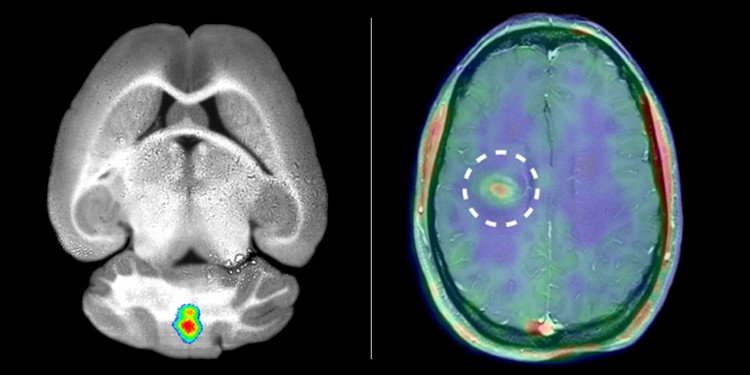

Behandlung durch HSZT für Multiple-Sklerose-Patienten

Behandlung durch HSZT für Multiple-Sklerose-Patienten from static.tildacdn.com